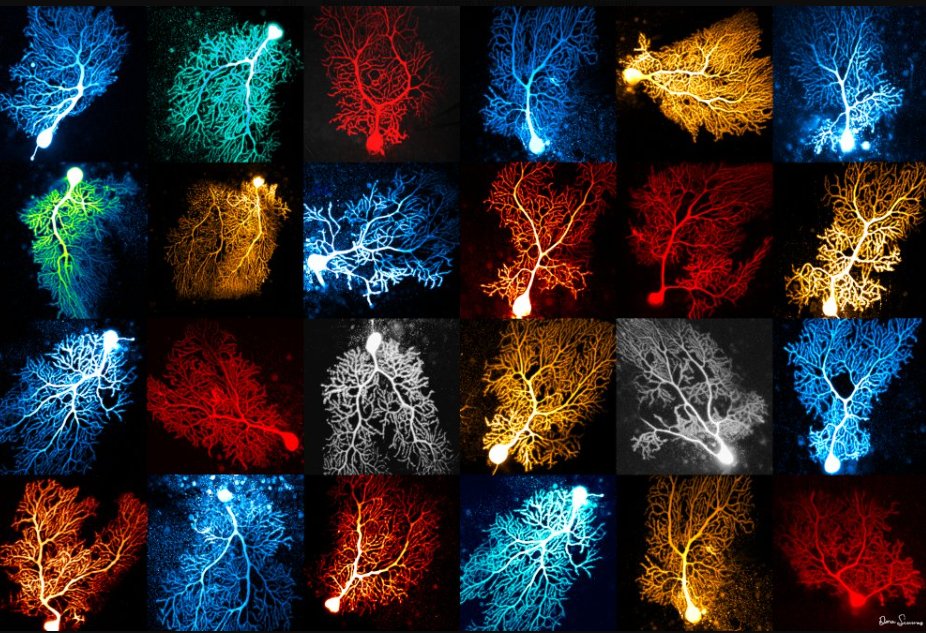

spinal cord injury research x web3 ⚡Radiology NFTs 🧠 🦴 collect NFTs to fund neuroRecovery research 🔬#paralysis #neuroscience #blockchain #nft #deSci #web3

A research team with Texas A&M AgriLife Research & @tamu has found a way to effectively deliver protein to the brain with therapeutic & scientific implications. Repairing spinal cord injuries & other localized injections are some of the potential uses for the method. tx.ag/InjectedProtein